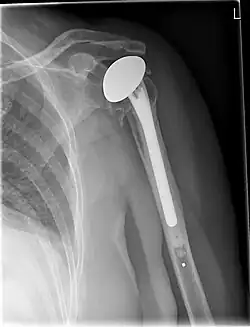

X-ray of a shoulder prosthesis

Various materials can be used to make prostheses, however the majority consist of a metal ball that rotates within a polyethylene (plastic) socket. The metal ball takes the place of the patient's humeral head and is anchored via a stem, which is inserted down the shaft of the humerus. The plastic socket is placed over the patient's glenoid and is typically secured to the surrounding bone via cement.[13]